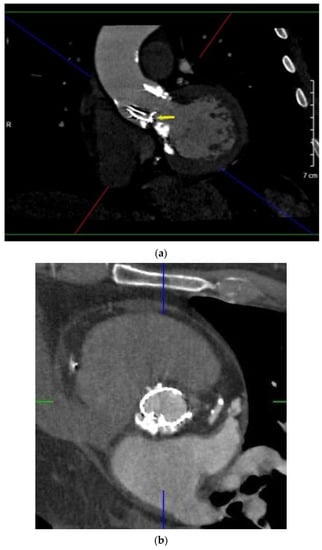

Male, 69 y/o, with hypertension, hypercholesterolemia and previous myocardial infarction. He was affected by severe degenerative aortic stenosis and underwent trans-catheter aortic valve replacement (TAVR) with LOTUS Edge 27 mm in April 2020. TTE performed a few days after the TAV implantation detected an increased transprosthesis gradient (maximum/median gradient, 78/52 mm Hg) in the absence of fever or positive hemoculture. TEE showed hypomobility of the noncoronary cusp of the bioprosthesis (Supplementary Video S4). Valve’s thrombosis was suspected and heparin administration was started. MDCT detected a paravalvular leak caused by misfolding of the prosthesis’ frame; the suspicion of valve thrombosis was also confirmed by the finding of two hypodense appositions at the lower edge of the valve. The patient underwent balloon valvuloplasty with complete resolution of the valvular dysfunction (Figure 4a–c).

Figure 4.

Oblique MPR (a), axial (b) and 3D anatomical model (c) of transcatheter PHV (LOTUS Edge 27 mm) focusing on its frame’s partial crumpling (arrow). A cluster of calcifications can be noted under the PHV.

In case 4, the 3D anatomical model provided by MDCT clarified the stent’s frame’s crumpling morphology, guiding the choice of the right tools for angioplasty. MDCT integrated with metal artifact reduction filters plays an important role in determining the morphology and location of the frame’s misfolding in percutaneous valves [20,22,23], caused by native aortic valve/annulus calcifications, valve undersizing or mal-positioning [2].